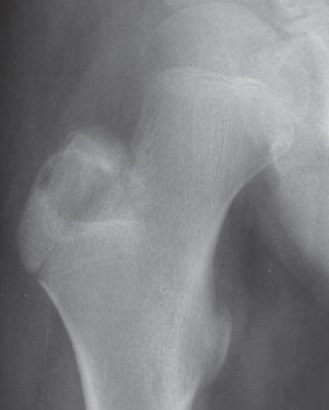

34

Qual diagnóstico?

Áreas radiolucente em região ilíaca esquerda Artrose Espessamente cortical *** Áreas líticas e blásticas dx: doença de Paget

35

Qual o diagnóstico?

Exsudatos algodonosos no crânio dx: Doença de Paget

36

Lesões líticas e blásticas Curvatura da tíbia * pode ser encontrado curvatura do fêmur também dx: doença de Paget